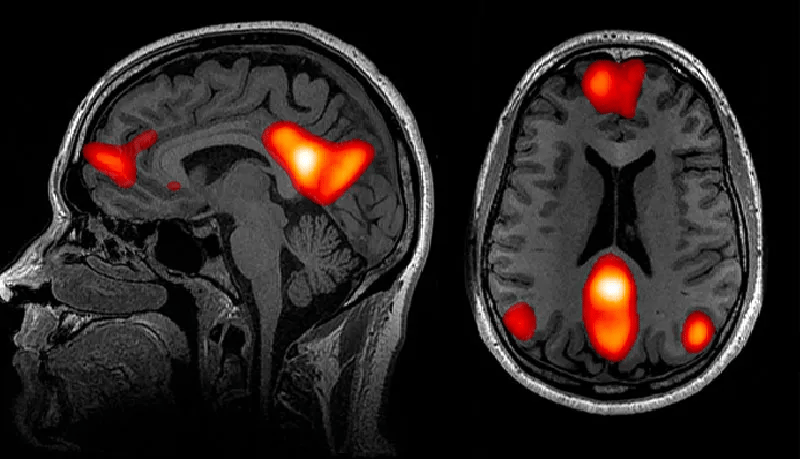

Loneliness doesn’t just feel bad, it hurts your brain.

Scientists can literally see it on scans:

🔸 Memory shrinks. Loneliness makes it harder to learn new things and recall old ones.

🔸 Stress stays high. Constant cortisol slowly burns brain cells and wears you down.

🔸 Grey matter fades. Your focus gets weaker and decisions become harder.

This is why when you’re lonely, it’s harder to think straight, remember simple things, or even make good choices.